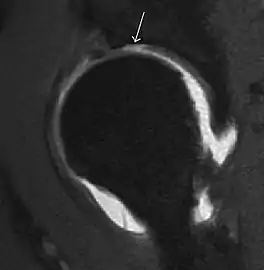

Synovial chondromatosis can be confidently diagnosed by X-ray when calcified cartilaginous chondromas are seen. However, other synovial proliferative processes, such as pigmented villonodular synovitis, require MRI for accurate diagnosis, although noncalcified synovitis can be suspected in radiographs by indirect signs, such as soft tissue swelling and/or erosions in the femoral head, femoral neck, or acetabulum (Figure 7).[1]

Figure 7:

Axial CT image of pigmented villonodular synovitis eroding the posterior cortex of the femoral neck.[1]

Sagittal T2* gradient echo image showing a posterior soft tissue mass with hypointense areas secondary to hemosiderin deposition.[1]

In synovial proliferative disorders, MRI demonstrates synovial hypertrophy. In the case of PVNS, characteristic foci of low signal intensity related to hemosiderin deposition are better seen on gradient echo T2* images (Figure 7). In the case of synovial osteochondromatosis, the synovial hypertrophy is accompanied by intermediate signal cartilaginous loose bodies and/or low signal calcified loose bodies.[1]